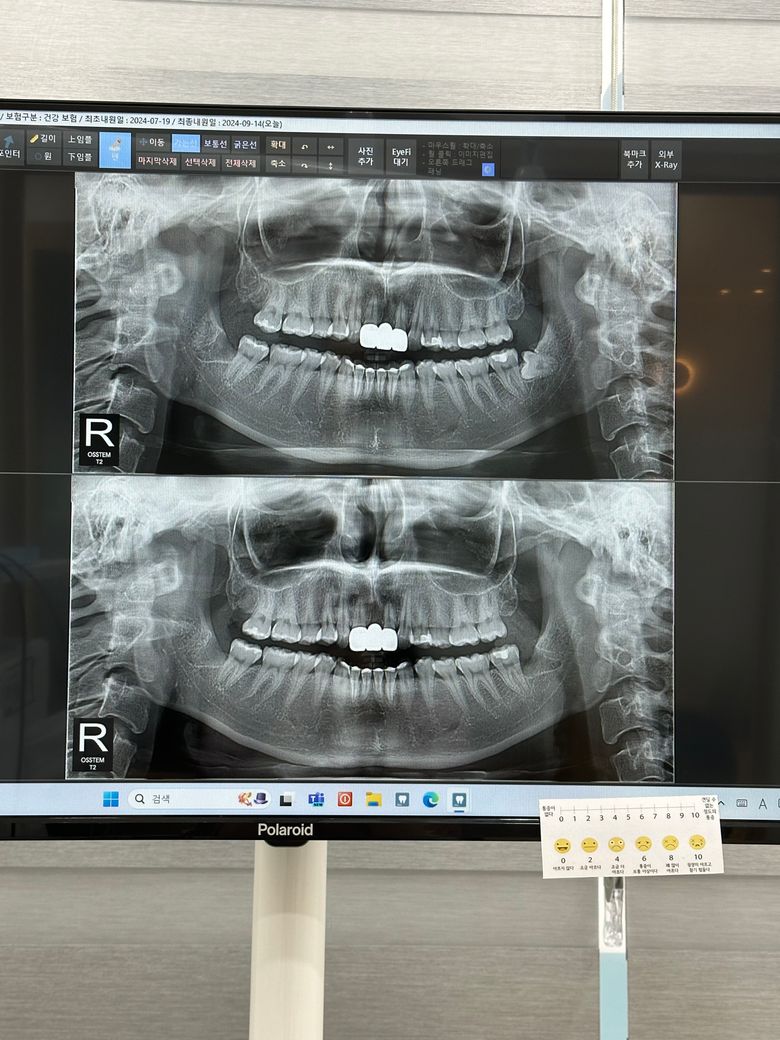

사랑니 발치 3주후 하얀 뼈가 보이는데 괜찮나요?

사랑니 발치후 3정도 됏고 2주전에 실밥 풀었어요

하얀게 계속 보여서 밥풀인가 하고 혼자 낑낑대다 근처 동네 치과갓더니 뼈라고하던데..

문제가 안되나요?

현재 사진을 보면 잘 낫고 있는 것으로 보입니다. 뼈가 보이는 부분도 시간이 지나면 아물겁니다.

잇몸뼈가 보이는건 아니고 잇몸이 아물면서 생기는 자연스러운 현상이니 너무 걱정하지 않으셔도 될것같습니다.

정상 치유 과정입니다 잇몸살이 완전히 덮히기 위해서는 1~2달 이상이 걸리기도 합니다 해당부위 음식물이 안끼게 되도록 관리를 잘해주시기 바랍니다

발치 후 상처가 치유되면서 뼈가 노출될 수 있습니다. 뼈가 노출이 되더라도 치유가 되고 있기에 문제가 되지 않으며, 만약 붓기나 통증이 동반되는 경우에는 치과 진료를 받길 권합니다.